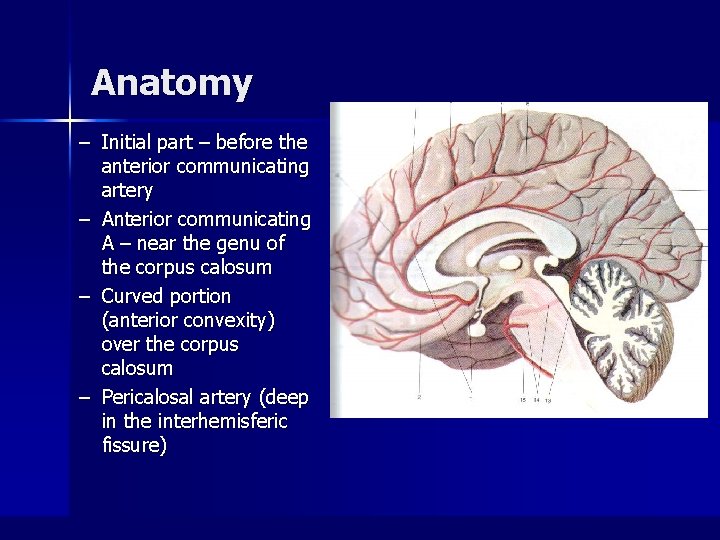

Anatomy – Initial part – before the anterior communicating artery – Anterior communicating A – near the genu of the corpus calosum – Curved portion (anterior convexity) over the corpus calosum – Pericalosal artery (deep in the interhemisferic fissure)